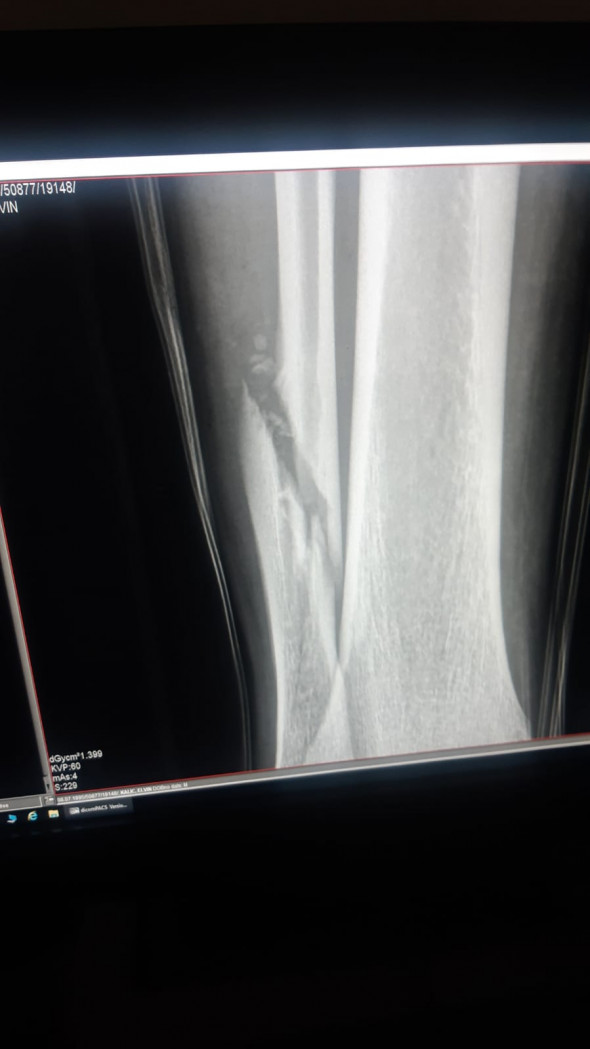

La scurt timp după intrarea dură a lui Mihalache, jucătorul Universității Craiova a început să urle de durere și a fost transportat de urgență la spital. Diagnosticul pus de medici a fost fractură de peroneu.

„Elvir Koljic a fost operat cu succes astăzi și peste 3 zile va începe procesul de recuperare”, scrie pe pagina oficială de Facebook al clubului din Bănie.

Elvir Koljic s-a accidentat pentru prima oară când evolua la Lech Poznan. A doua oară la naţionala Bosniei, imediat după ce fusese introdus pe teren. A treia oară şi a patra oară în tricoul Craiovei, într-un meci la Voluntari şi vineri, după o intrare tare a lui Mihalache. Cele patru accidentări grave ale lui Elvir Koljic sunt în decurs de 3 ani. Unul dintre cei mai ghinionişti jucători din lume. Bosniacul are fractură de peroneu şi va rata tot acest sezon.